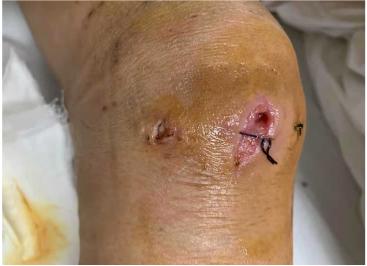

令人头痛的是,这个药好像也没有特别有效:膝盖还是红肿,有块地方红得越来越厉害,终于破出了个小口,渗出了一大股脓液,擦去脓液,一个深深的洞赫然出现,洞壁上粉红的肉看得老两口心惊胆战。

此时陶阿姨的膝盖仍然肿得厉害,加上表面的破溃,活像一个被剜去了一块的西瓜,让她苦不堪言。正好是假期刚结束,病房床位不太紧张,陶阿姨很快就住进了病房。